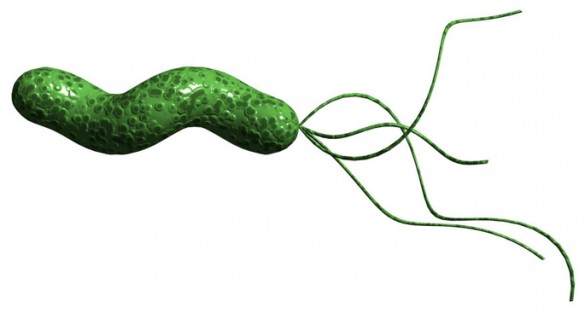

The investigators found that in addition to its known ability to block the production of cell growth compounds, the drug DFMO (difluoromethylornithine) acts directly on the bacterium Helicobacter pylori to reduce its virulence. H. pylori infection is the primary cause of gastric cancer.

H. pylori infects the stomachs of half of the human population, but only about 1 percent of infected individuals develop stomach cancer. Although it’s possible to treat the infection to prevent stomach cancer, it’s not clear whom to treat. Plus, the bug may be conferring beneficial effects — esophageal reflux diseases, asthma and other allergic disorders occur more frequently in people who are not infected with H. pylori.

“H. pylori has co-evolved with humans for at least 60,000 years, probably longer, and attempting to prevent stomach cancer by eliminating the infection with widespread use of antibiotics is not necessarily a good idea,” said Keith Wilson, MD, Thomas F. Frist Sr. Professor of Medicine and professor of Pathology, Microbiology and Immunology.

To further explore how DFMO works, J. Carolina Sierra, PhD, research instructor in Medicine, collected H. pylori bacteria from infected animals that had been treated (or not) with DFMO. Using an in vitro test, she assessed the activity of one of the main H. pylori virulence factors, a protein called CagA. CagA is “injected” into stomach epithelial cells, where it contributes to oncogenic signaling pathways.

The researchers discovered that DFMO treatment — in animals or in vitro — caused mutations in the H. pylori gene that encodes CagY, part of the translocation machinery that injects CagA into cells.